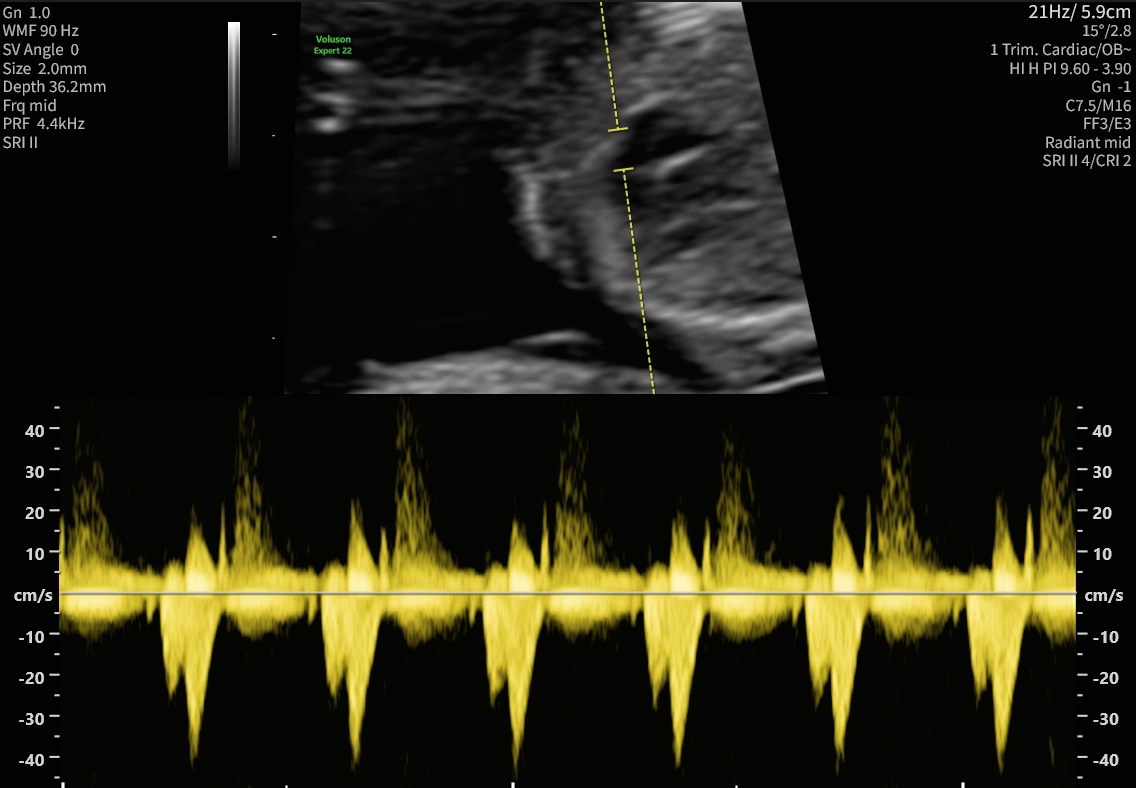

Zusätzliche Kriterien sind die Messung des kindlichen Nasenbeins, Beurteilung des Blutflusses über den Herzklappen und Messung des venösen Blutflusses zum kindlichen Herzen hin. Parallel dazu können aus einer mütterlichen Blutprobe zwei Schwangerschaftshormone (freies ß-HCG und PAPP-A) analysiert werden. Besonders hohe oder niedrige Konzentrationen sind als Risiko für das mögliche Vorliegen von Chromosomenveränderungen und einer Reihe weiterer Erkrankungen zu werten. Aus den biochemischen Ergebnissen, den Ultraschalldaten und Ihren persönlichen Daten wird ein individuelles Risiko für Chromosomenstörungen in der vorliegenden Schwangerschaft errechnet.